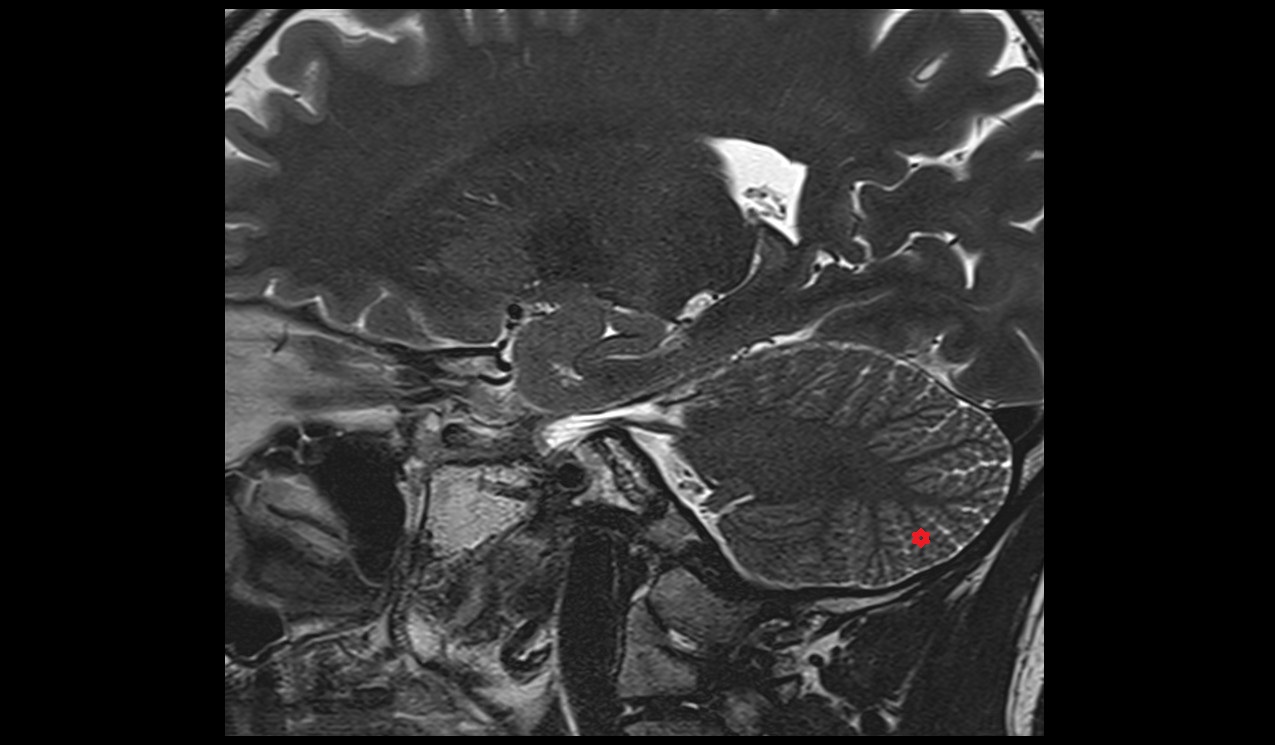

- Cerebellum